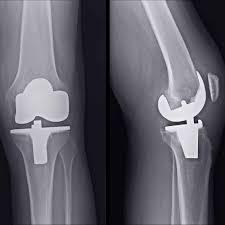

Total Knee Replacement in Amaravti

Severe knee pain, arthritis, and joint degeneration can limit daily activities and affect overall quality of life. For patients in Amaravti suffering from advanced knee problems, total knee replacement (TKR) offers a reliable solution to restore mobility, reduce pain, and improve independence. With modern surgical techniques and structured post-operative care, patients can experience lasting relief and enhanced joint function.

Moreover, total knee replacement involves precise evaluation, surgical planning, and rehabilitation, which together ensure long-term success. Patients who choose skilled orthopedic care benefit from advanced implants, minimally invasive procedures, and customized recovery programs that accelerate healing and improve outcomes.